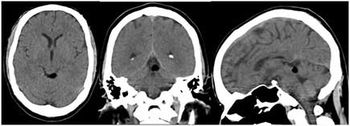

Tectal Plate Lipoma

Case History: 37-year-old female with headaches.